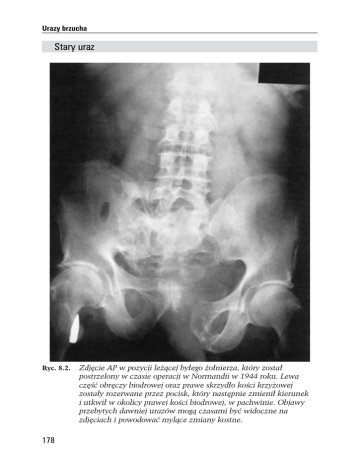

Urazy brzucha Stary uraz Ryc. 8.2. 178 Zdjêcie AP w pozycji le¿¹cej by³ego ¿o³nierza, który zosta³ postrzelony w czasie operacji w Normandii w 1944 roku. Lewa czêœæ obrêczy biodrowej oraz prawe skrzyd³o koœci krzy¿owej zosta³y rozerwane przez pocisk, który nastêpnie zmieni³ kierunek i utkwi³ w okolicy prawej koœci biodrowej, w pachwinie. Objawy przebytych dawniej urazów mog¹ czasami byæ widoczne na zdjêciach i powodowaæ myl¹ce zmiany kostne. Uraz wielonarz¹dowy: klatki piersiowej i brzucha Uraz wielonarz¹dowy: klatki piersiowej i brzucha Szukaj (ryc. 8.3): • Ca³kowitego oddzielenia dolnej czêœci krêgos³upa piersiowego oraz odpowiednich ¿eber; • Pêkniêcia lewej kopu³y przepony z oddzieleniem od œciany klatki piersiowej; • Z³amania górnych ¿eber oraz obustronnej odmy podskórnej; • Okrê¿nicy w klatce piersiowej; • Odmy op³ucnowej w zakresie podstawy p³uca lewego; • Przemieszczenia serca na prawo; • Worków piasku stabilizuj¹cych g³owê. Dziecko zmar³o z powodu wspó³istniej¹cych ciê¿kich obra¿eñ g³owy. Ryc. 8.3. Czteroletnie dziecko, które zosta³o wyrzucone z samochodu, kiedy ten uderzy³ w drzewo. Nie mia³o zapiêtych pasów. Dozna³o wielu ciê¿kich urazów i zginê³o. 179